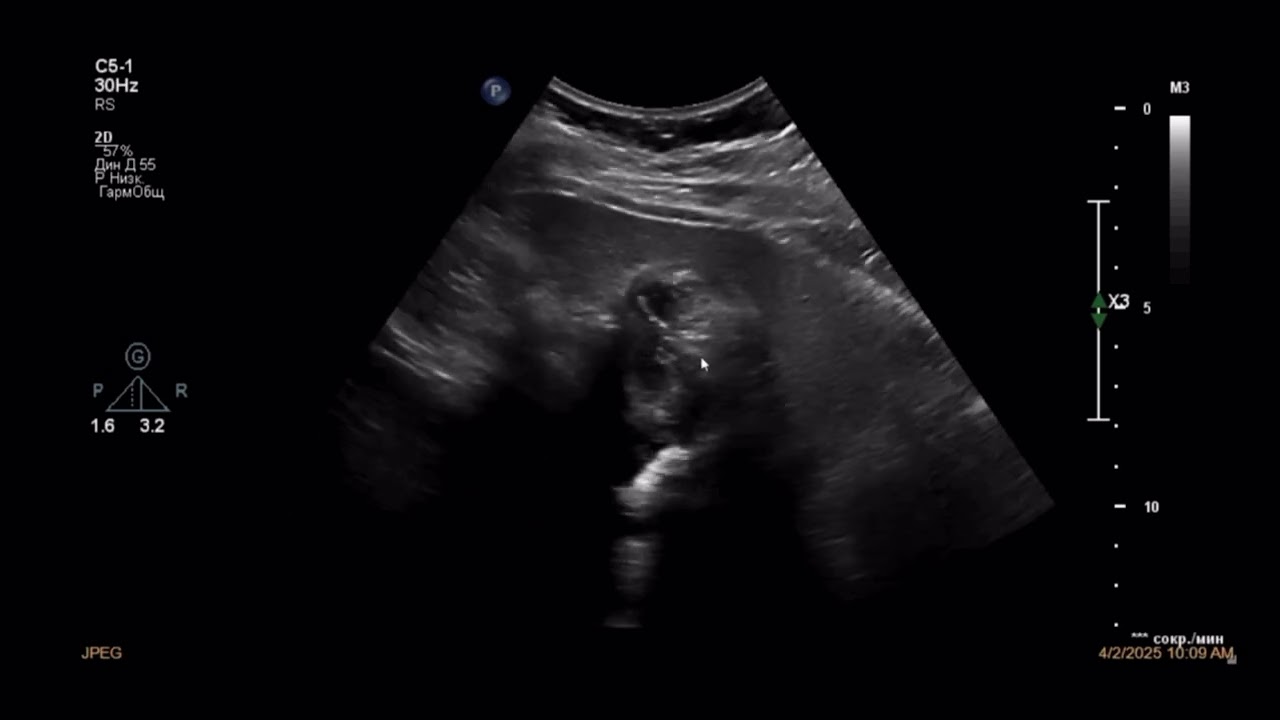

Жёлчный пузырь:

Форма правильная (грушевидная), размеры в пределах нормы (длина XX мм).

Стенка не утолщена (до 2.5 мм), контур ровный.

В просвете визуализируется гиперэхогенное неоднородное содержимое, очень медленно смещаемое —соответствует билиарному сладжу.

На фоне сладжа определяются мелкие гиперэхогенные включения размером до 2-3 мм,

без акустической тени.

Перивезикулярная клетчатка — без изменений.

Признаков жидкости, отёка или локальной болезненности при давлении датчиком не выявлено (симптом УЗ-Мерфи отрицательный).

Заключение:

Билиарный сладж с микролитами.

Рекомендуется консультация гастроэнтеролога.